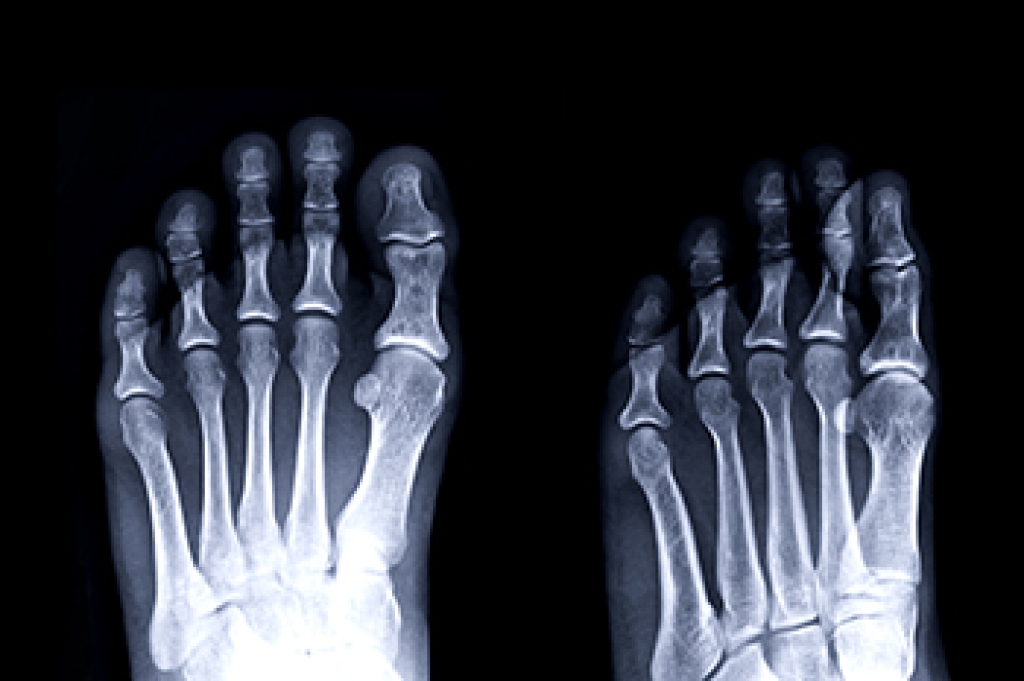

Diabetic foot care is essential for anyone with diabetes, as high blood sugar can lead to nerve damage, called neuropathy, and poor circulation. These issues make it harder to feel injuries or detect infections, which can lead to serious complications, if untreated. Symptoms include numbness, tingling, or a burning sensation in the feet. You might also notice cuts, blisters, or ulcers that heal slowly, along with swelling or redness. If left untreated, infections can worsen, leading to more severe conditions, including limb loss. To prevent complications, daily foot inspections are critical. It is important to look for cuts, sores, or swelling. Keep your feet clean and dry, wear properly fitted shoes, and avoid tight socks. Controlling your blood sugar and avoiding smoking can improve circulation. A podiatrist can help with regular foot exams and early detection of wounds or ulcers. This foot doctor also can provide treatment for existing issues like wound care or prescribe custom orthotics for better foot alignment. For comprehensive diabetic foot care, it is suggested that you schedule an appointment with a podiatrist.

Diabetes affects millions of people every year. The condition can damage blood vessels in many parts of the body, especially the feet. Because of this, taking care of your feet is essential if you have diabetes, and having a podiatrist help monitor your foot health is highly recommended.